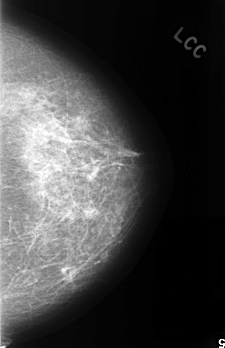

C_0338_1.LEFT_CC

LEFT_CC LINES 4512 PIXELS_PER_LINE 2920 BITS_PER_PIXEL 12 RESOLUTION 50 NON_OVERLAY